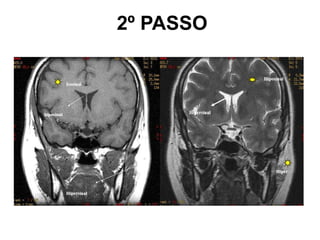

2º PASSO

• Imagem branca 

Hipersinal

• Imagem preta 

Hipossinal

• Imagem cinza 

Isossinal

Cuidado!!!!

• As imagens brancas nem

sempre significam que

possuem uma alta

quantidade de H+, pois

as imagens podem ser

com tonalidades

invertidas (ponderações).